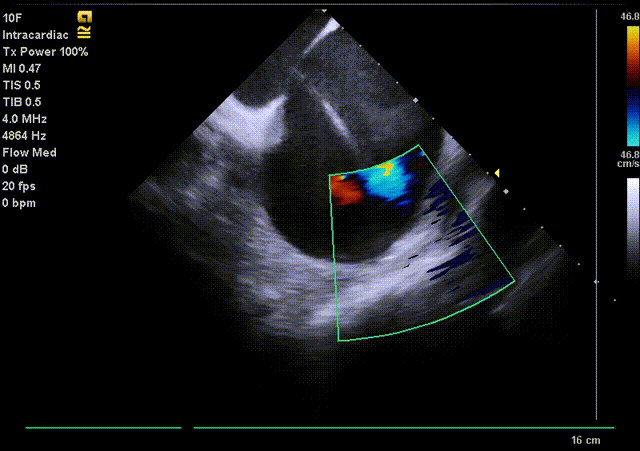

通过ICE再次确认LAA无血栓,并指导房间隔穿刺位置;

通过ICE进行LAA血栓筛查

使用ICE观察无残余分流,封堵盘未遮挡肺静脉及二尖瓣;

封堵盘展开后ICE观察